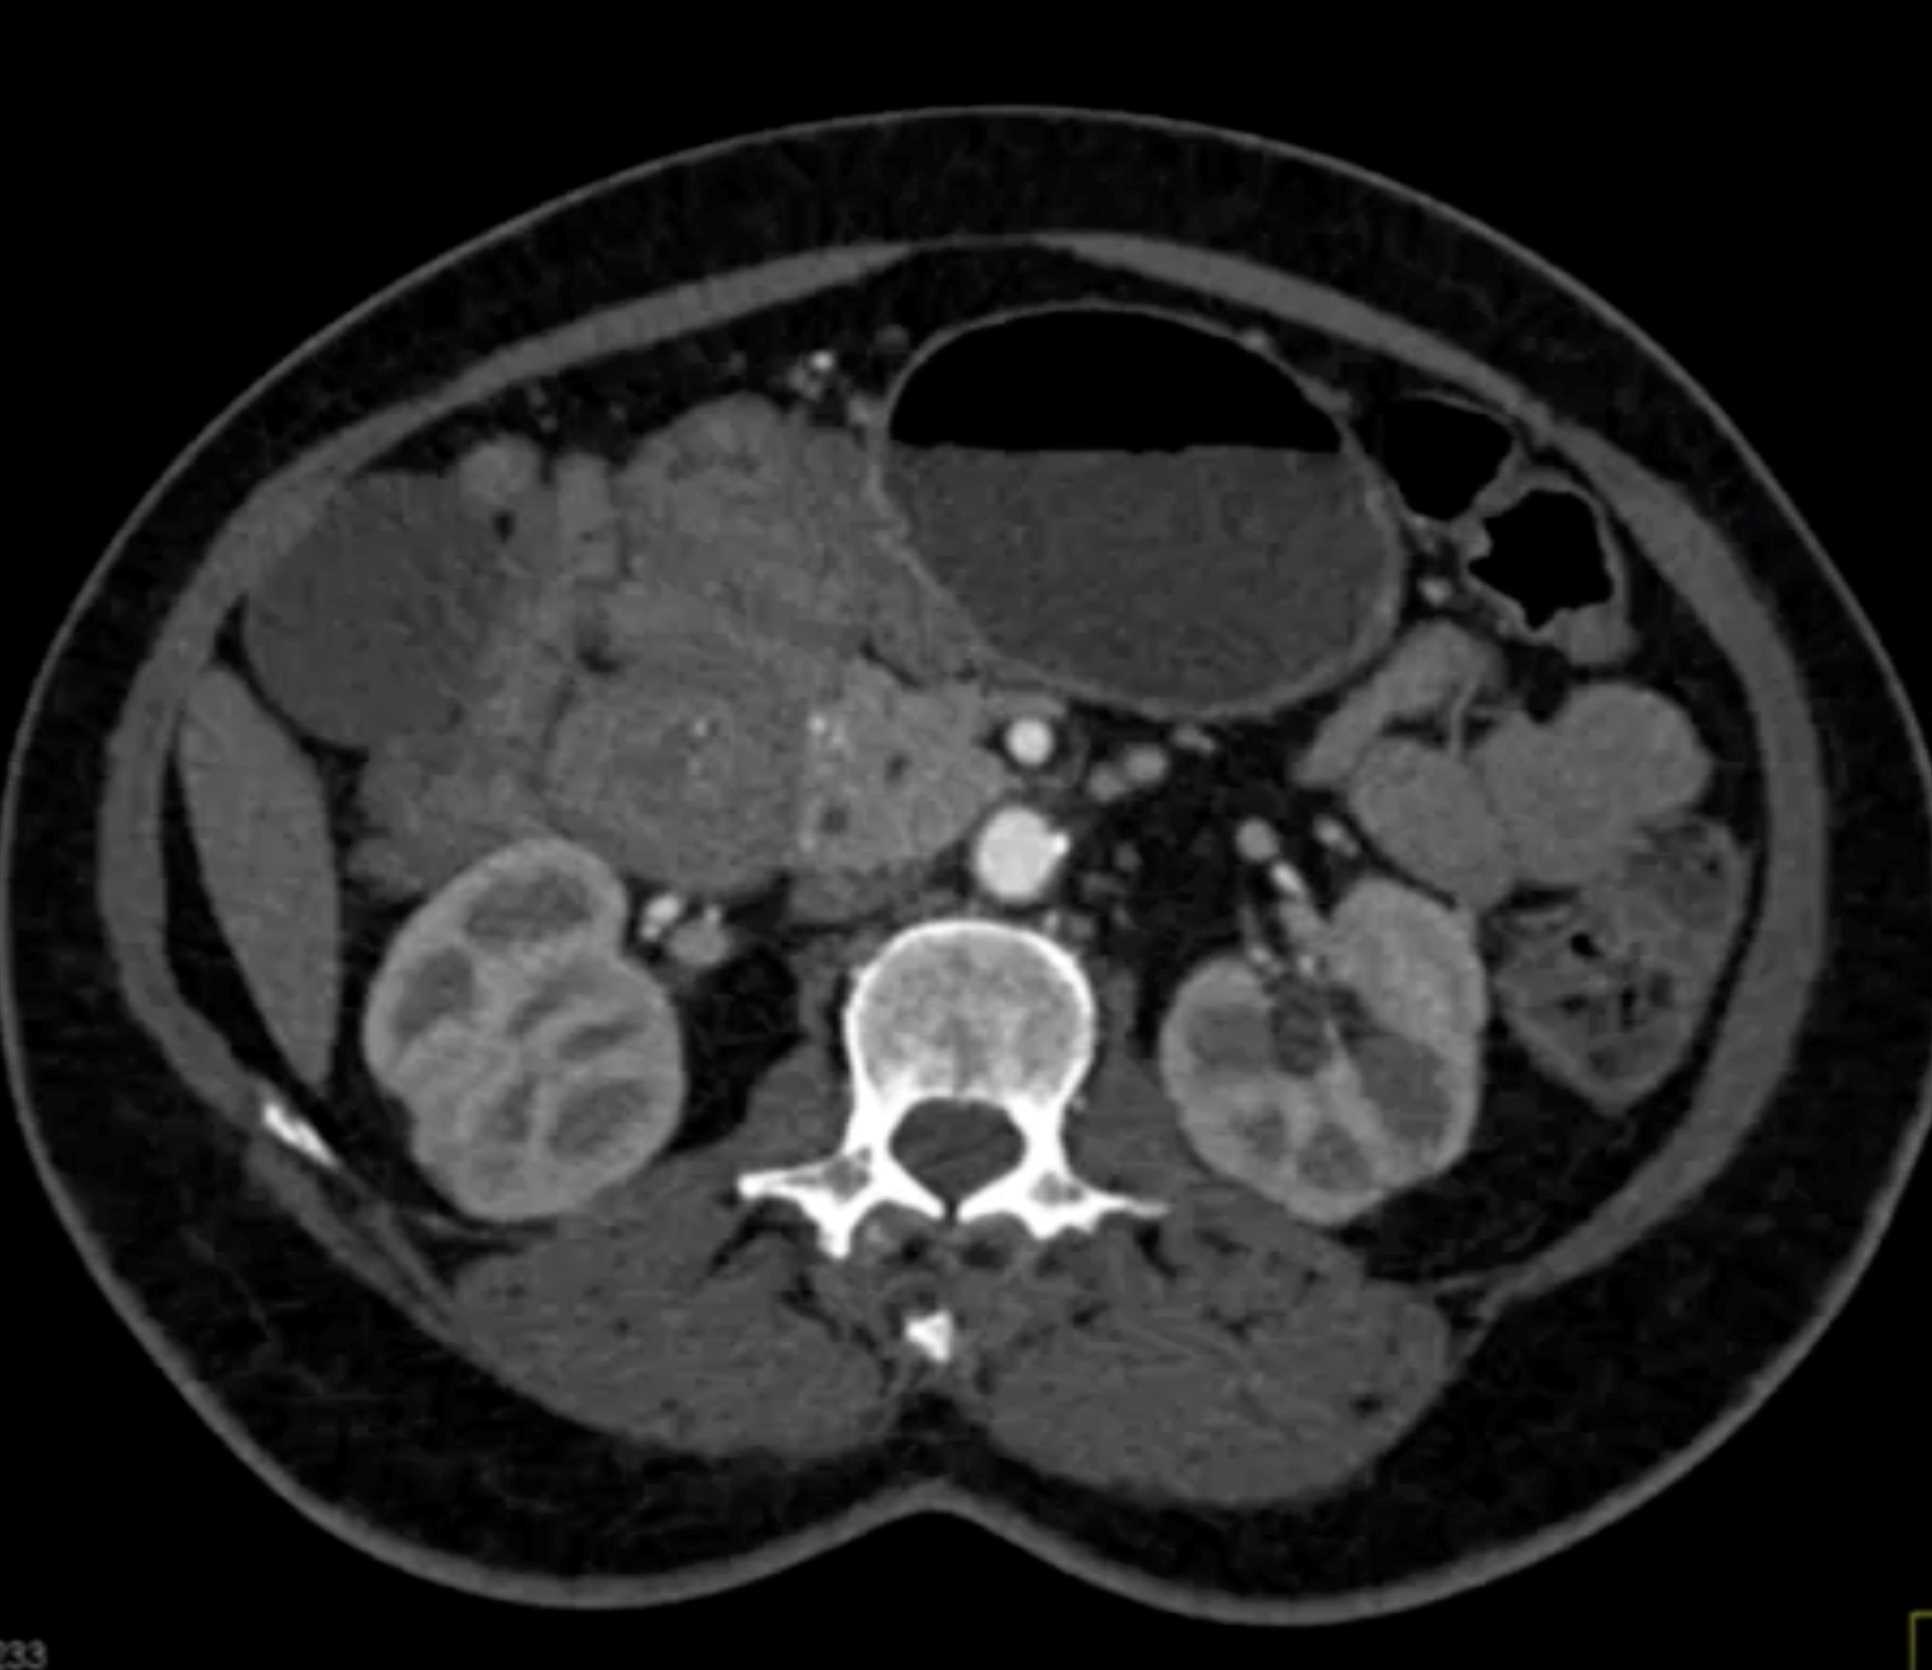

Lagre Gastric GIST Tumor